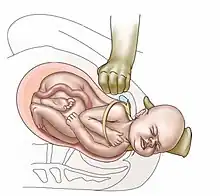

| Suprapubic pressure being used in a shoulder dystocia | |

- Anterior shoulder disimpaction (suprapubic pressure);[11]